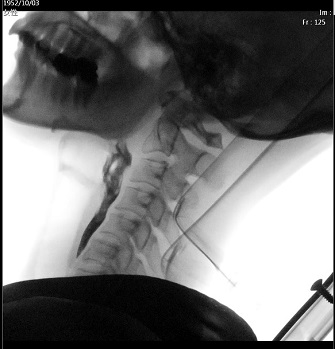

VF(嚥下造影検査)

造影剤入りの検査食を飲み込んでいただき、X線透視装置を用いて動画撮影し、誤嚥や残留の有無や障害部位を評価します。